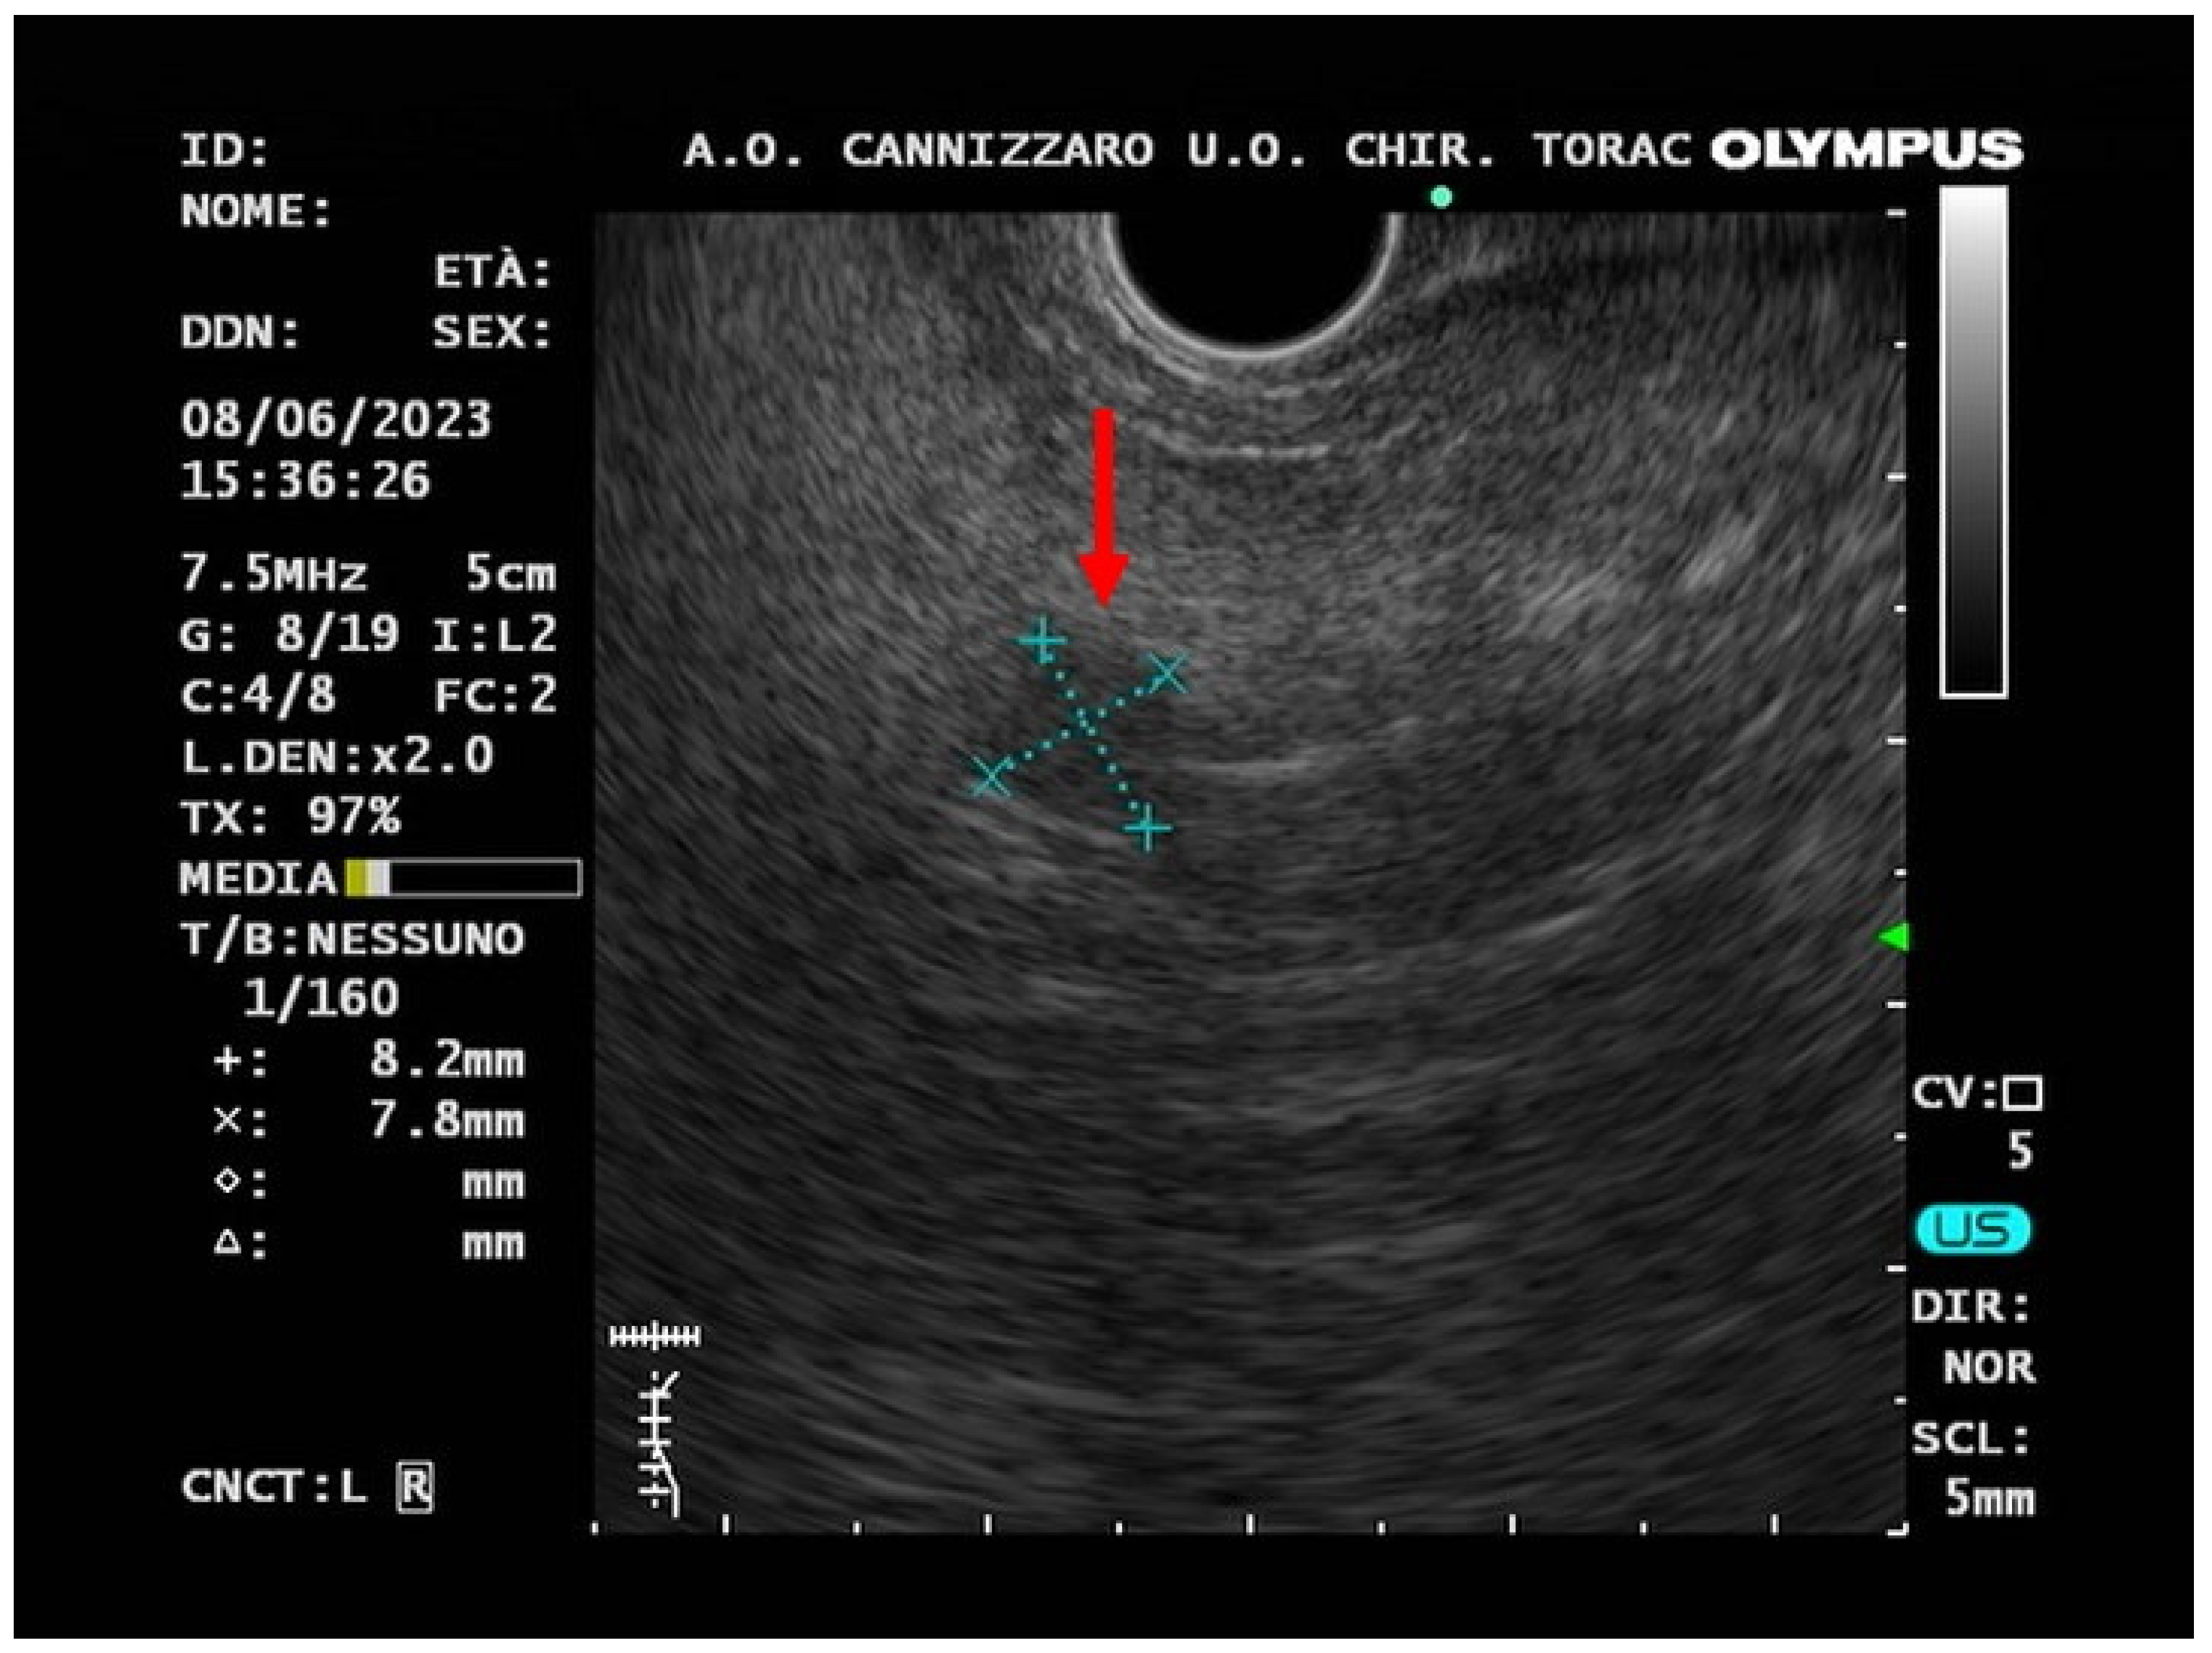

2. Case-Report